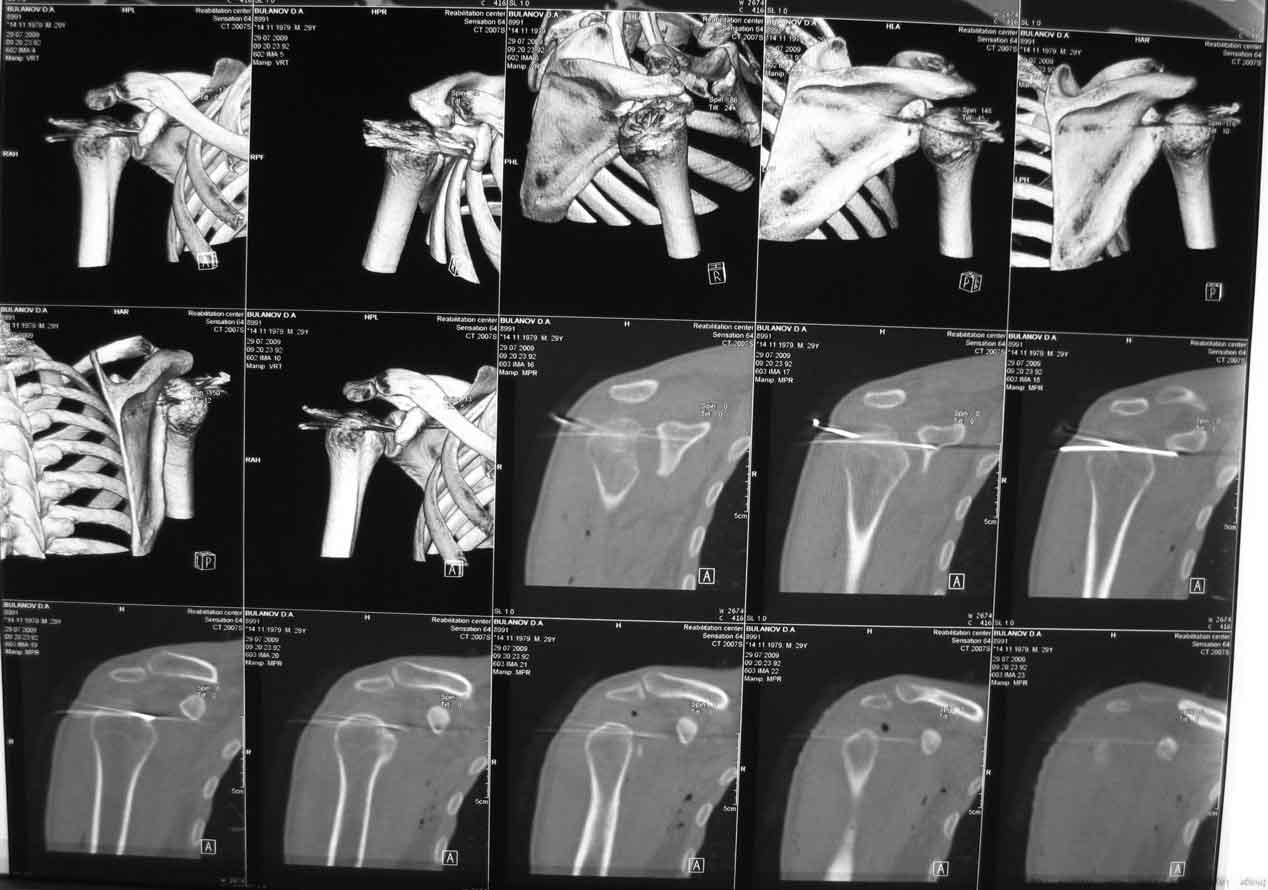

Вот послеоперационная КТ.

Рука в бандаже у живота.

Кликните для загрузки файла 1kt.jpg